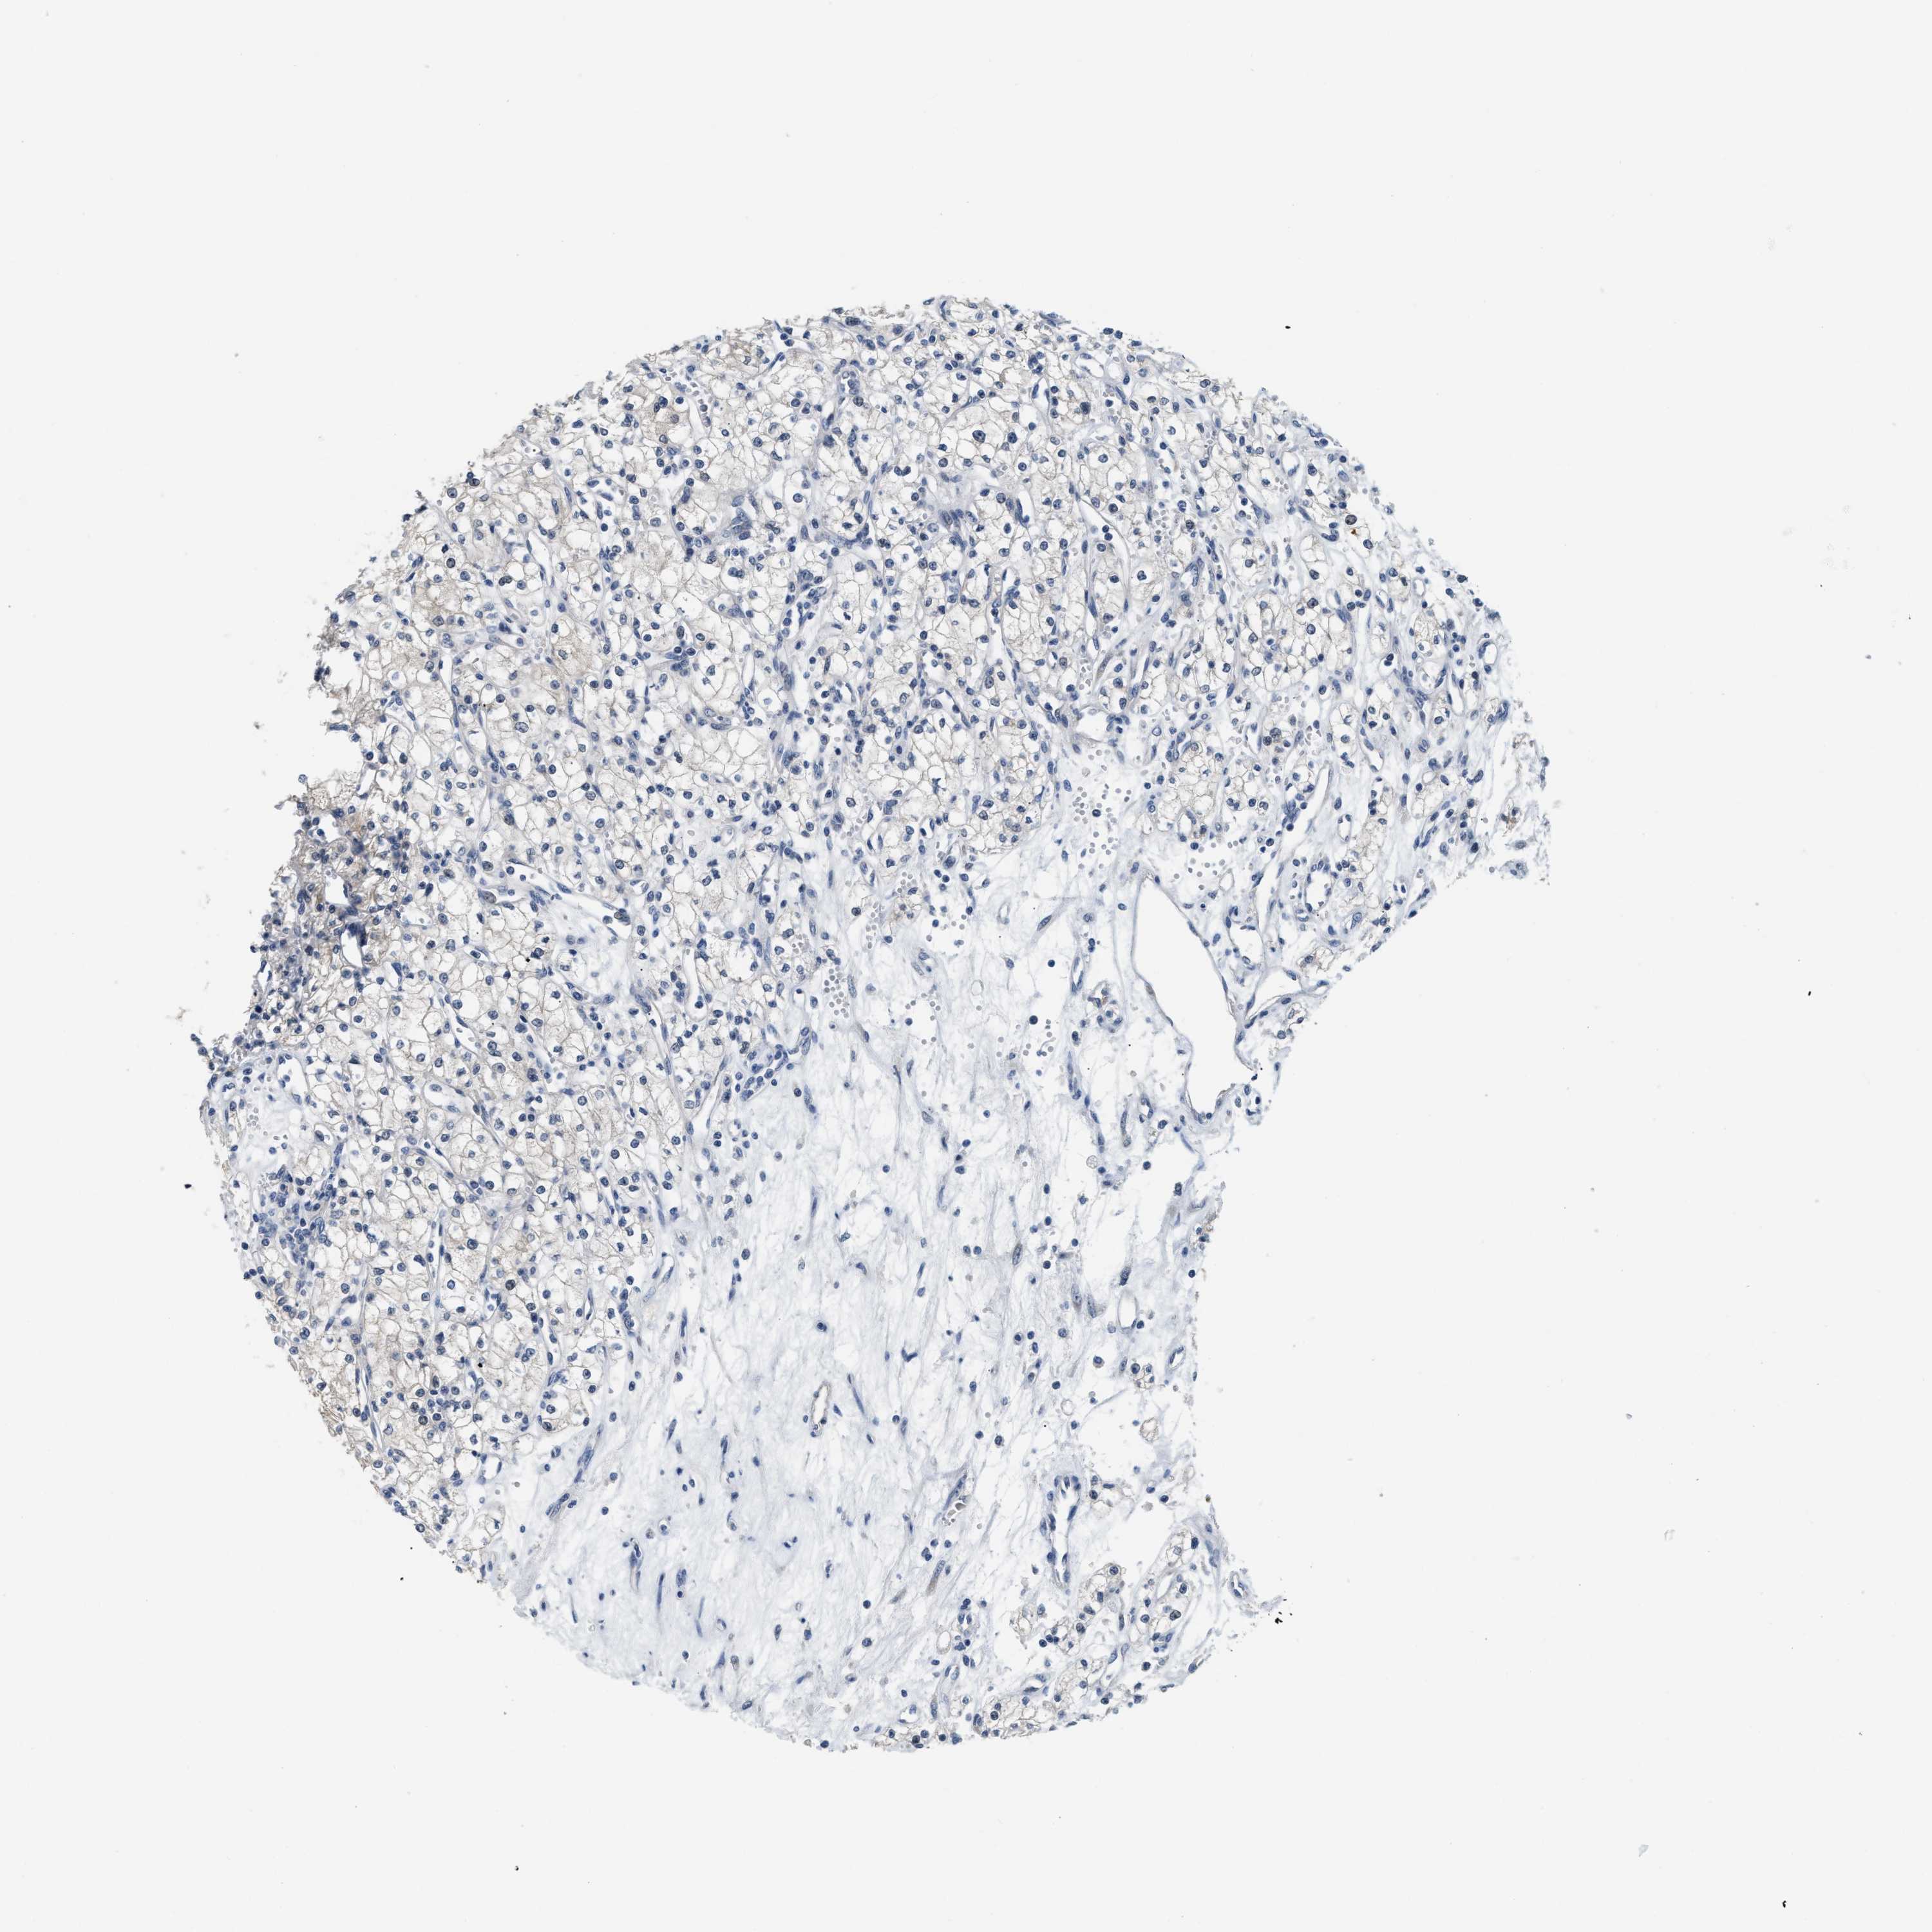

KIDNEY RENAL CLEAR CELL CARCINOMA (VALIDATION) - Interactive survival scatter ploti

The Survival Scatter plot shows the clinical status (i.e. dead or alive) for all individuals in the patient cohort, based on the same data that underlies the corresponding Kaplan-Meier plots. Patients that are alive at last time for follow-up are shown in blue and patients who have died during the study are shown in red.

The x-axis shows the expression levels (FPKM) of the investigated gene in the tumor tissue at the time of diagnosis. The y-axis shows the follow-up time after diagnosis (years). Both axes are complimented with kernel density curves demonstrating the data density over the axes. The top density plot shows the expression levels (FPKM) distribution among dead (red) and alive patients (blue). The right density plot shows the data density of the survived years of dead patients with high and low expression levels respectively, stratified using the cutoff indicated by the vertical dashed line through the Survival Scatter plot. This cutoff is automatically defined based on the FPKM cutoff that minimizes the p-score. The cutoff can be changed by dragging the vertical line or by entering a cutoff value in the square labeled "Current cut-off".

Under the Survival Scatter plot the p-score landscape (black curve; left axis) is shown together with dead median separation (red curve; right axis). Dead median separation is the difference in median mRNA expression between patients who have died with high and low expression, respectively. It is calculated as follows: median FPKM expression of dead patients with high expression - median FPKM expression of dead patients with low expression. This is intended to aid the user in visually exploring custom cutoffs and the associated p-scores and dead median separation.

Individual patient data is displayed and can be filtered by clicking on one or more of the category buttons on the top of the page. Categories describing expression level and patient information include: high, low, alive, dead, female, male and tumor stages. The scale of the x-axis can be toggled between linear and log-scale by clicking on the "x log" button. Mouse-over function shows TCGA ID, patient information and mRNA expression (FPKM) for each patient.

& Survival analysisi

Kaplan-Meier plots summarize results from analysis of correlation between mRNA expression level and patient survival. Patients were divided based on level of expression into one of the two groups "low" (under cut off) or "high" (over cut off). X-axis shows time for survival (years) and y-axis shows the probability of survival, where 1.0 corresponds to 100 percent.

CLGN is not prognostic in Kidney Renal Clear Cell Carcinoma (validation)

Best expression cut offi

: 0.53

Average pTPM 2.6

Number of samples 100